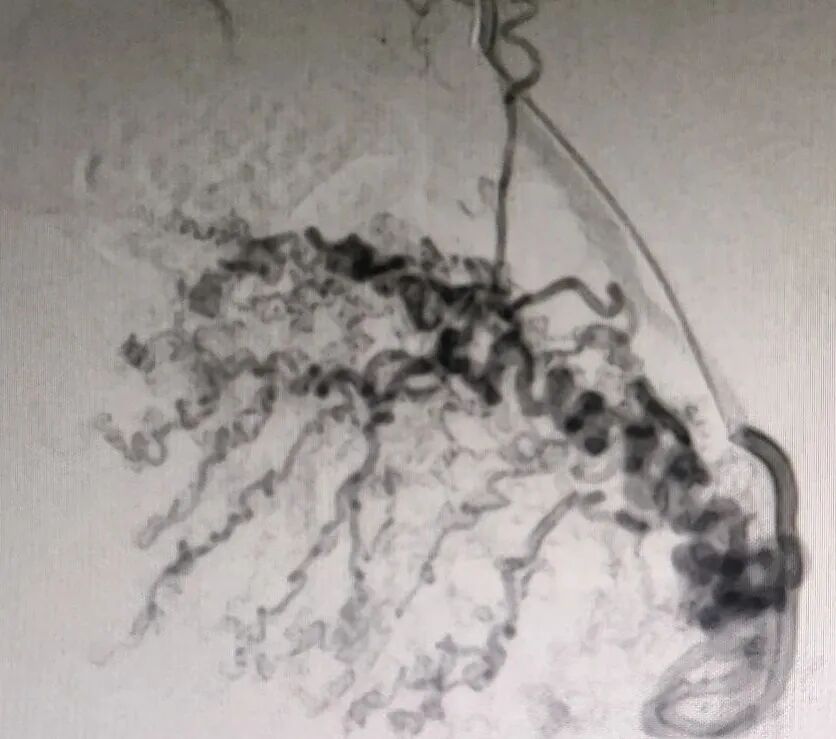

术后影像

图片   图片